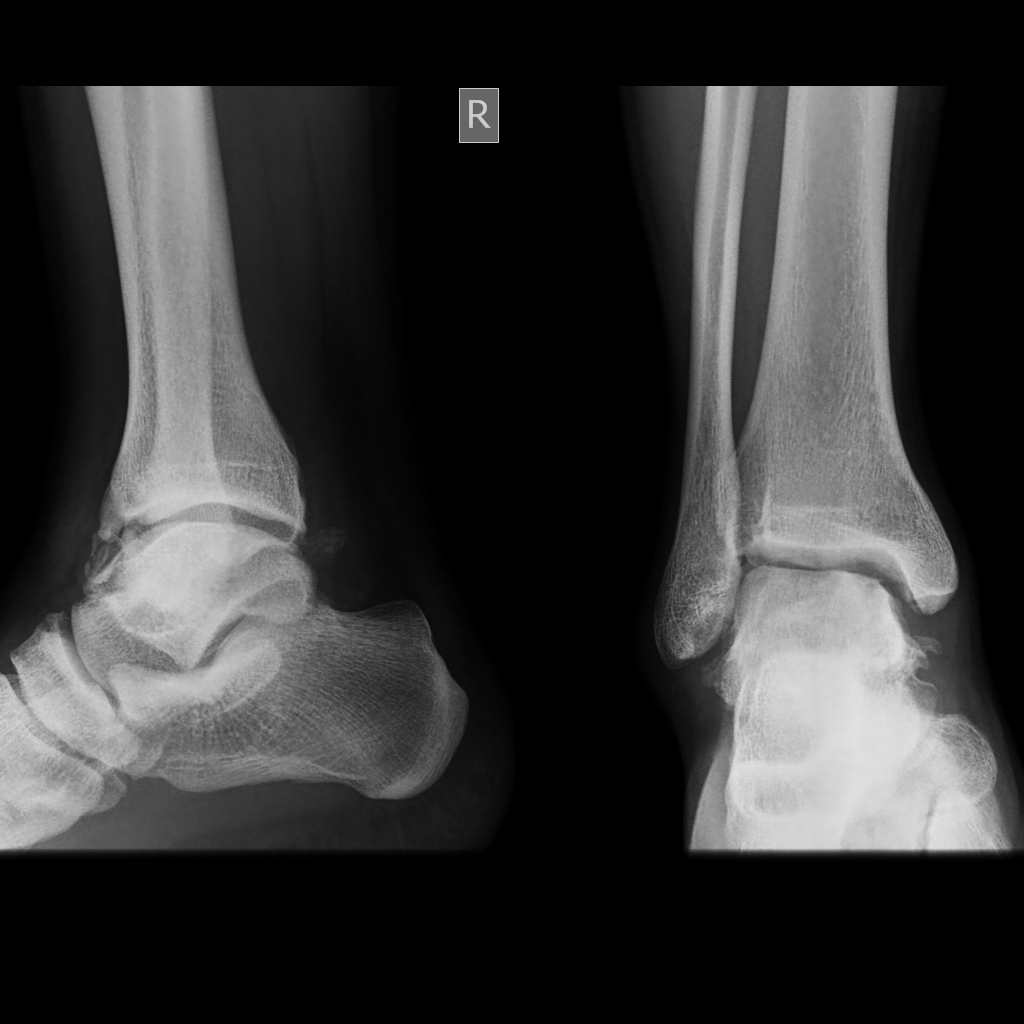

Footballer's Ankle Xray . Footballer's ankle is a pinching or impingement of the ligaments or tendons of the ankle between the bones, particularly the talus and tibia. Standard ankle radiographs are necessary and are the mainstay of imaging anterior ankle impingement. Anterior ankle impingement, originally nicknamed “footballer’s ankle” and later known as “athlete’s ankle” is a source of chronic. The treatment for anterior impingement in the ankle can include physical therapy to help improve the range of motion and break down. Anterior ankle impingement (footballer's ankle) is a painful pinching or compression of either the soft or the bony tissue at the front of your ankle. The xray view of the ankle from the side (lateral radiograph) shows. It is also to bear in.

Normal ankle joint, Xray Stock Photo, Royalty Free Image 26886997 Alamy Footballer's Ankle Xray Anterior ankle impingement, originally nicknamed “footballer’s ankle” and later known as “athlete’s ankle” is a source of chronic. Anterior ankle impingement (footballer's ankle) is a painful pinching or compression of either the soft or the bony tissue at the front of your ankle. Footballer's ankle is a pinching or impingement of the ligaments or tendons of the ankle between the. Footballer's Ankle Xray.

Ankle Xray Interpretation Ankle Fracture Geeky Medics Footballer's Ankle Xray Standard ankle radiographs are necessary and are the mainstay of imaging anterior ankle impingement. The treatment for anterior impingement in the ankle can include physical therapy to help improve the range of motion and break down. The xray view of the ankle from the side (lateral radiograph) shows. Anterior ankle impingement, originally nicknamed “footballer’s ankle” and later known as “athlete’s. Footballer's Ankle Xray.